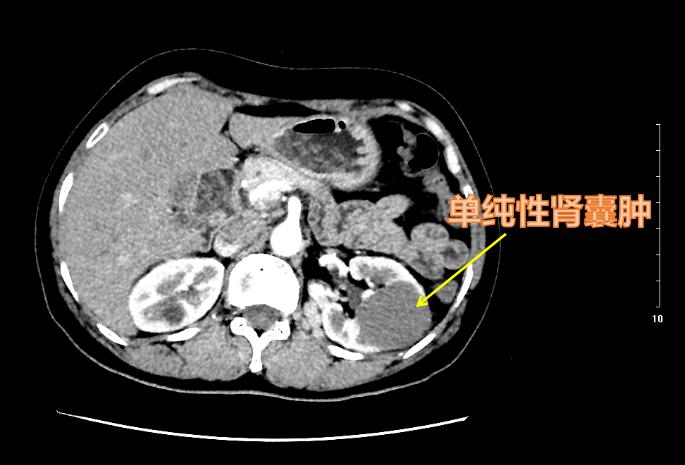

单纯性肾囊肿边界清晰,预后良好!